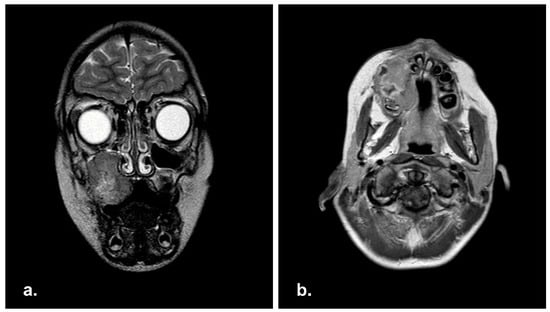

MRI showed a wide RMS (7.5 × 6 × 5 cm) involving the left masticatory space with maxillary sinus invasion. Left cheek and orbital floor were affected as well, and bilateral positive lymph nodes were detected (Figure 6).

Figure 6. Pre-operative Magnetic Resonance Imaging (MRI) in axial (a) and coronal (b) view with showing a massive neoplasia in the right masticatory space.